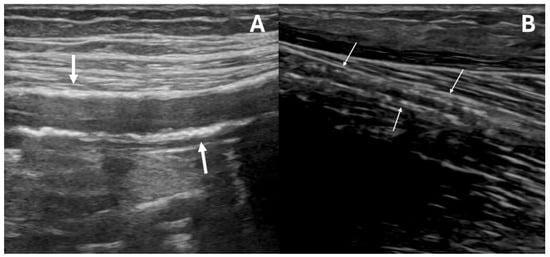

DUS scans were performed by the same experienced operator; the clinician was not involved in any eventual subsequent decision-making process, in the case of PAD or MACE development. All examinations were executed following a standardized protocol, according to the guidelines of the Society for Vascular Ultrasound for lower extremity arterial duplex examination [15] and employing the same US machine (LOGIQ S8 with XDclear, GE HealthCare Technologies Inc., Chicago, IL, USA) with a linear probe (frequency range 7–12 MHz). Both lower extremities were scanned: femoro–popliteal and BTK vessels were analyzed in transverse and longitudinal views. As a standard of care in our center, both B-Mode and color duplex evaluations were applied to acquire morphological and hemodynamic waveform characteristics, respectively [16,17]. MAC was diagnosed in the longitudinal view when multiple hyperechogenic spots (Figure 1A) or a calcified “railway” (Figure 1B) pattern were observed within the medial arterial layer, extending for at least 2 cm in the middle or distal segment of one or more BTK vessels [18]. These localizations, particularly the distal tracts (as shown in Supplementary Figures S2 and S3), were selected to ensure a uniform MAC assessment across patients, as evaluating the proximal segment of these vessels can be challenging, for example in subjects with a high Body Mass Index. According to the presence or absence of BTK MAC, patients were assigned to the MAC+ (MAC presence) or MAC− (MAC absence) cohort.

Figure 1.

Ultrasound appearance of below-the-knee medial arterial calcification (MAC). MAC can appear as multiple hyperechogenic spots within the arterial wall (early stage, (A)) or as a continuous, hyperechogenic “railway” (late stage, (B)), as shown by the white arrows. The ultrasound image was magnified threefold (×3) and focused on its upper portion.